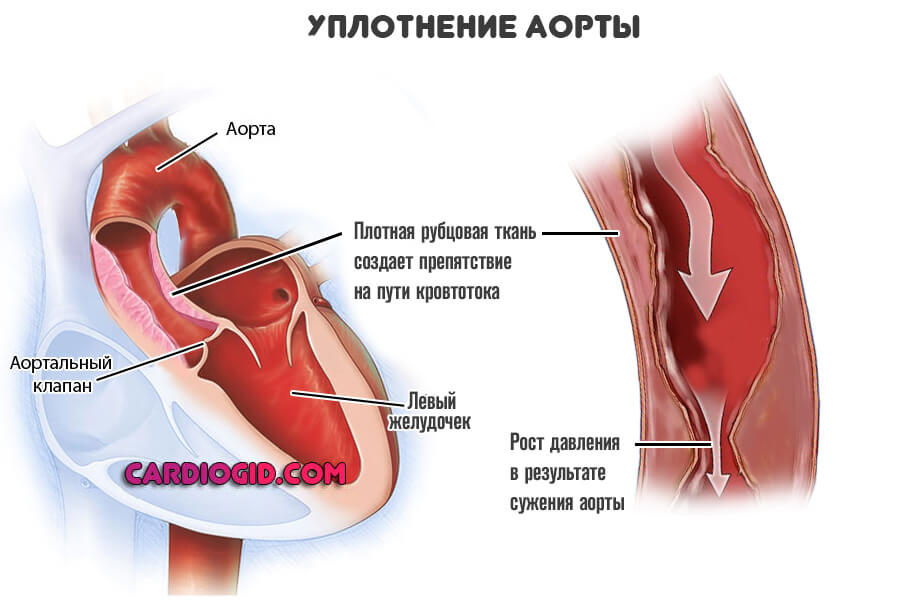

Нормальный диаметр корня аорты: медицинские нормы и отклонения